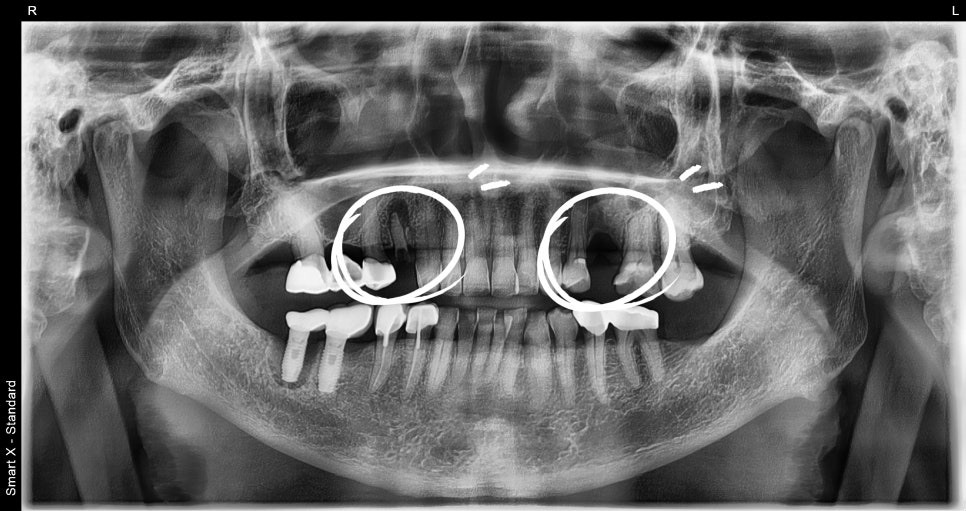

As a result of the panoramic X-ray and oral examination,

the alveolar bone condition was good, and it was possible to place insurance-covered implants.

① Detailed diagnosis and surgical planning

– A 3D CT scan was used to precisely analyze the nerve position and bone density.